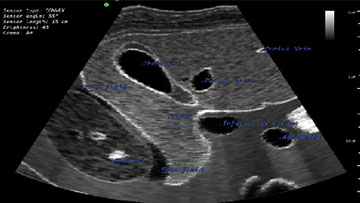

Библиотека учебных модулей включает упражнения, направленные на отработку процедур УЗИ органов малого таза (мужчина и женщина), брюшной полости и грудной клетки. Каждый клинический случай снабжается детализированным анамнезом для углубления процесса обучения.

Модуль по УЗИ органов брюшной полости и забрюшинного пространства

Модуль фокусированного УЗИ при травме (FAST протокол)

- Обучающий модуль по ультразвуковому исследованию органов брюшной полости и забрюшинного пространства

- Обучающий модуль фокусированного УЗИ при травме (FAST протокол